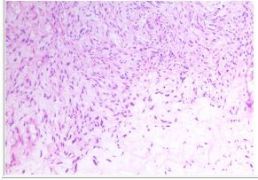

术中冰冻快速:梭形细胞肿瘤,细胞轻-中度异型,不除外恶性病变,待常规石蜡和免疫组化进一步明确。

病理明确,真相大白

经HE染色及免疫组织化学检测,IHC:CD10(灶区+),Vimetin(+),ER(2+),PR(0),S-100(-),SMA(部分+),WT1(-),CD34(灶区+),Caldesmon(-),Des(+),Ki-67(1%+),CD117(-),Dog-1(-)。双侧附件未见特异性病变。腹水检查未查见异常细胞。

图3:HE